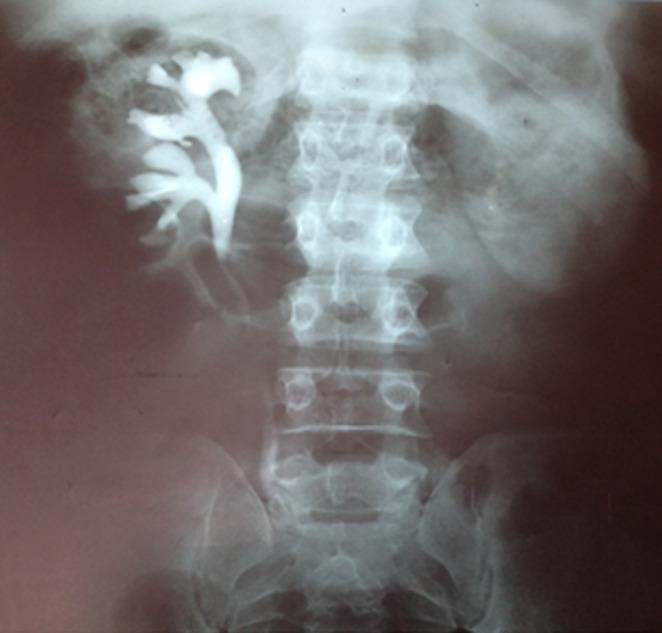

The purpose of this study is to highlight the role of open surgery in the treatment of patients with a history of extended and postinfectious ureteral stricture as well as our experience with therapy. The study involved a 38-year old patient presenting at the urology service of the University Clinics of Lubumbashi with left lumbar pain, burning sensation during urination and fever. Clinical and paraclinical assessment showed extended ureteral stricture. Temporary urinary diversion (left ureterostomy) was performed followed by ureterectomy and left ureterovesical reimplantation. The postoperative course was simple. Three months after surgery the patient had no complaints, creatinine levels were normal, ultrasound and uroscan results were normal.

https://cdn.ncbi.nlm.nih.gov/pmc/blobs/e058/8179988/89d6e789e45a/PAMJ-38-276-g001.jpg